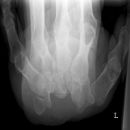

Hände nach Norgaard (Rheuma-Spezialaufnahme in der Medizin)

Lagerung

Pat. sitzt frontal am Tisch, Ellenbogen möglichst zusammen, Handinnenflächen zeigen nach oben, Finger leicht abgespreizt und gestreckt, Unterarm zur Tischoberfläche im Winkel von ca. 30° (-45°) (Ballauffang- o. Schalenhaltung). Beide Hände gleichzeitig zum Vergleich in einem Strahlengang.

Zentralstrahl

Senkrecht auf Kassettenmitte.

Anmerkung

Gute Projektion der kleinen Gelenke und Gelenkspalten.

Qualitätskriterien

Guter Einblick in die Gelenke.